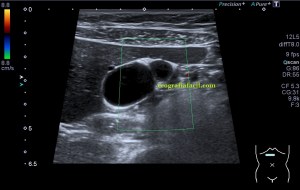

Bien, hemos visto una lesión que es un quiste hidatídico calcificado, pero te preguntarás, si nunca viste uno, ¿cómo es uno cuando tiene «hijas»?, es decir, cuando está activo…Mira este corte transversal de un hígado:

La LOE es de aspecto redondeado, heterogéneo, con multitud de pequeñas imágenes anecoicas e hipoecogénicas, de diferentes tamaños. Esta lesión fue estudiada también mediante otra técnica de imagen, la RMN donde se observa una imagen hiperdensa, con una amalgama de lesiones bordeando a periferia de la misma, de distintos tamaños como se objetiva en la imagen del mismo paciente, de la ecografía inmediatamente superior (Imagen 7). La lesión es activa, por tanto debió de ser tratada, la patología es potencialmente mortal en caso de que el quiste se rompiese.